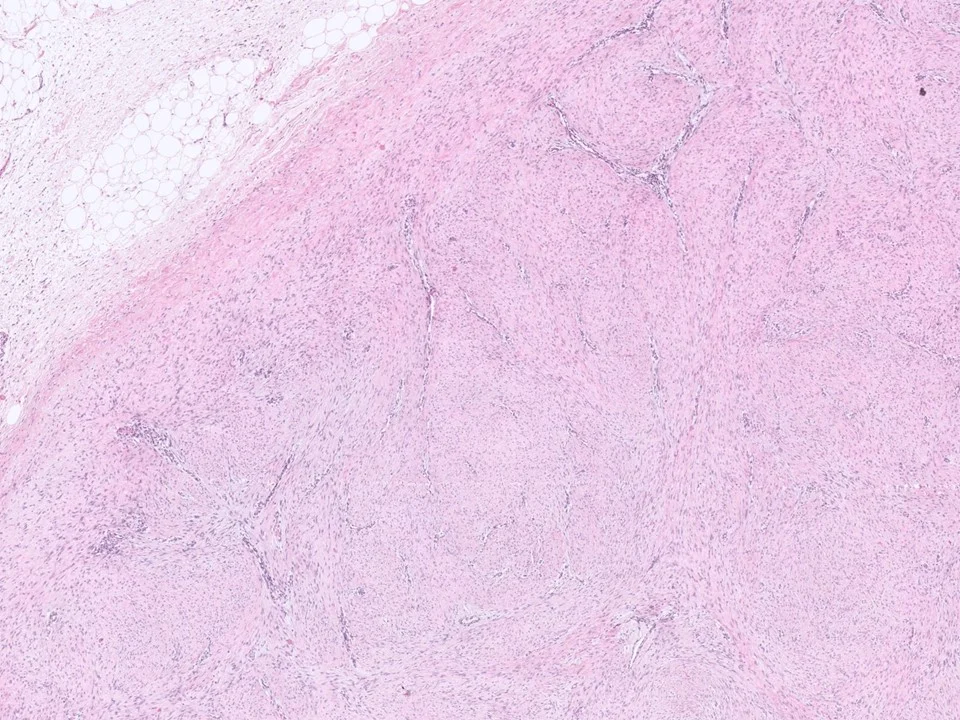

Fibromatosis

mammary fibromatosis is an infiltrative, locally aggressive proliferation of fibroblasts and myofibroblasts.

Histologically, mammary type fibromatosis is similar to desmoid-type fibromatosis in other sites. It is composed of uniform, bland spindle cells with pale eosinophilic cytoplasm, poorly defined cell borders, and oval to elongated and tapering nuclei. These cells can be seen infiltrating the stroma in long sweeping fascicles. Mitotic figures are usually not frequent. These lesions stain for beta-catenin.